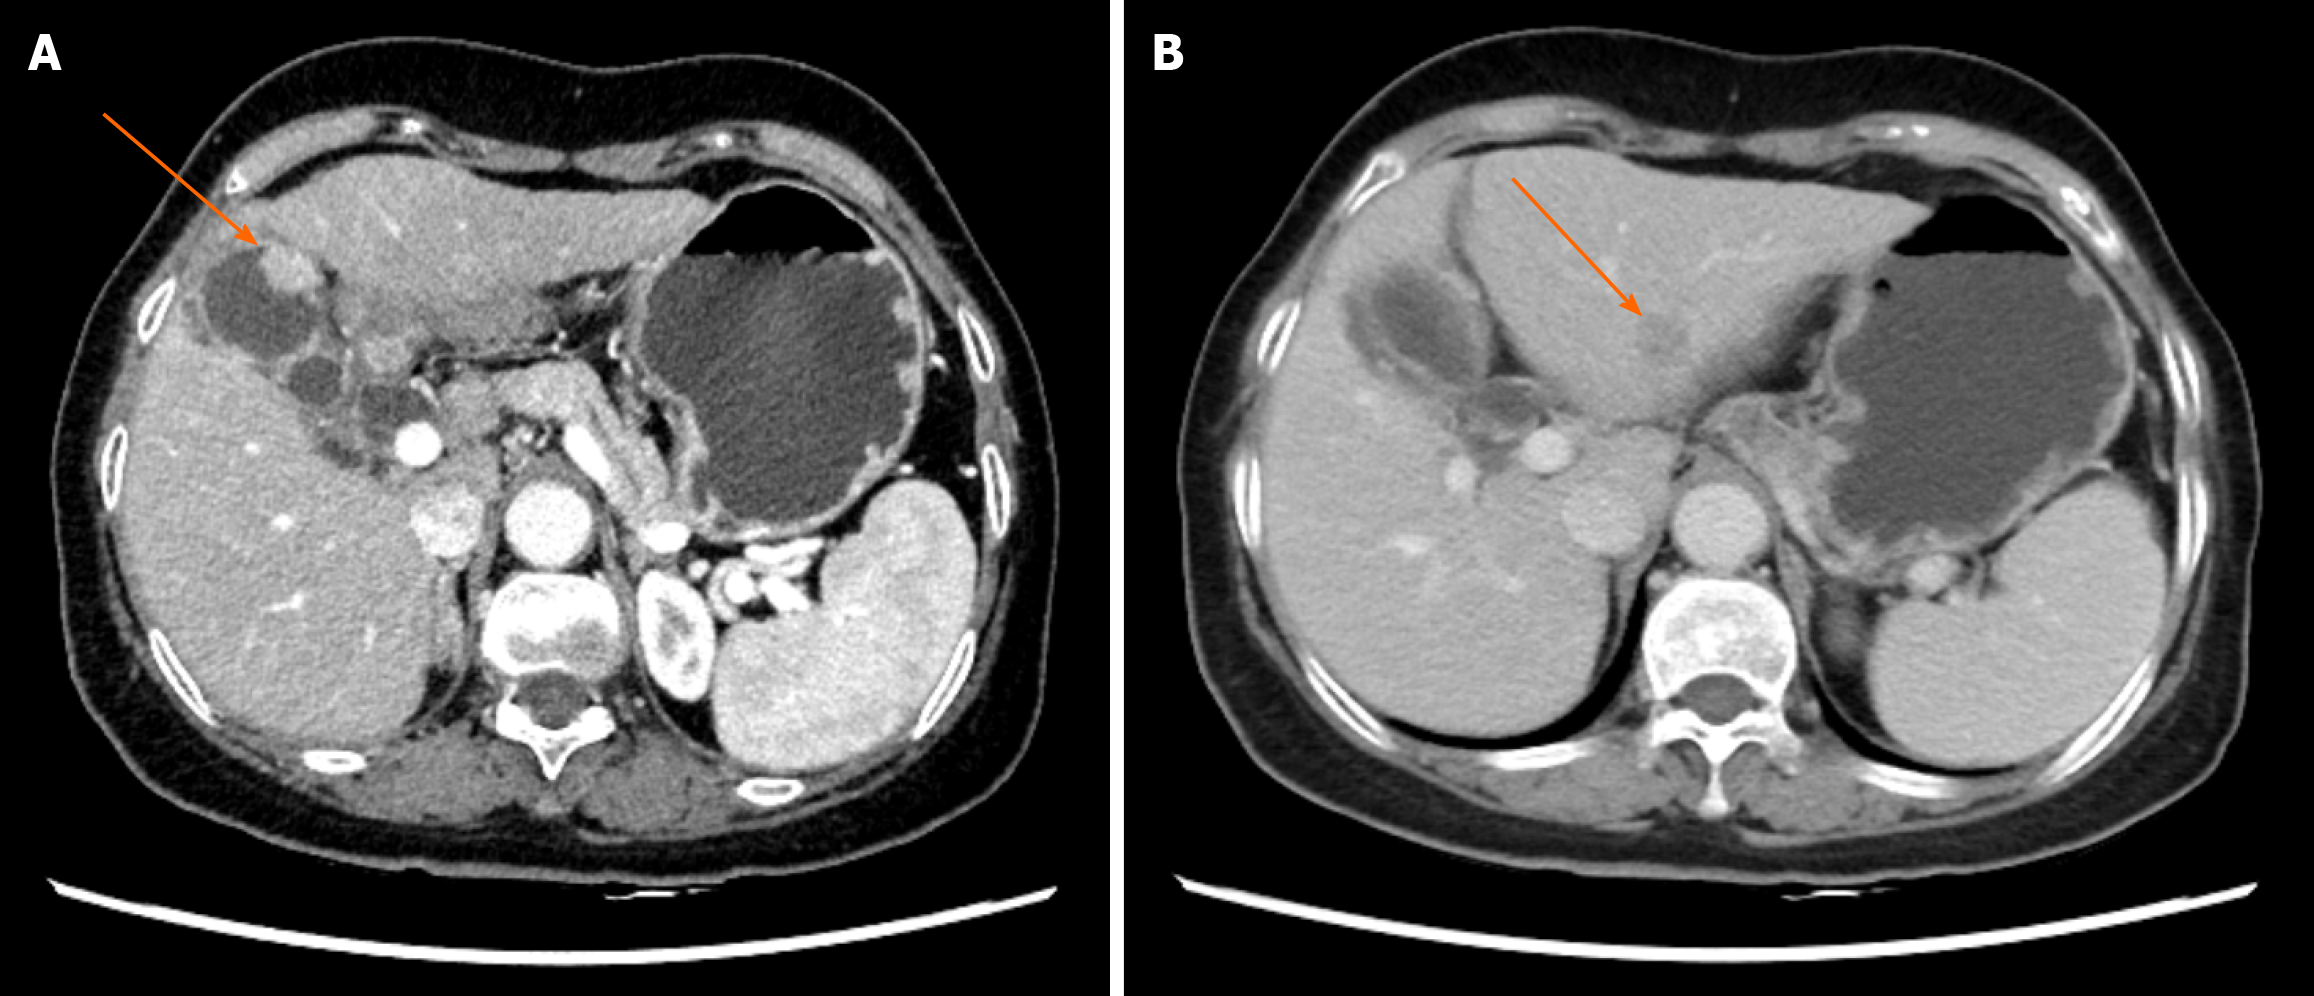

Figure 1 Abdominal computed tomography.

A: Abdominal computed tomography showing a 2.0 cm × 1.0 cm mass in the gallbladder. Arrow: Gallbladder mass (axial view); B: Abdominal computed tomography showing a 1.6 cm × 1.5 cm lesion in the left lateral lobe of the liver. Arrow: Liver lesion (axial view).